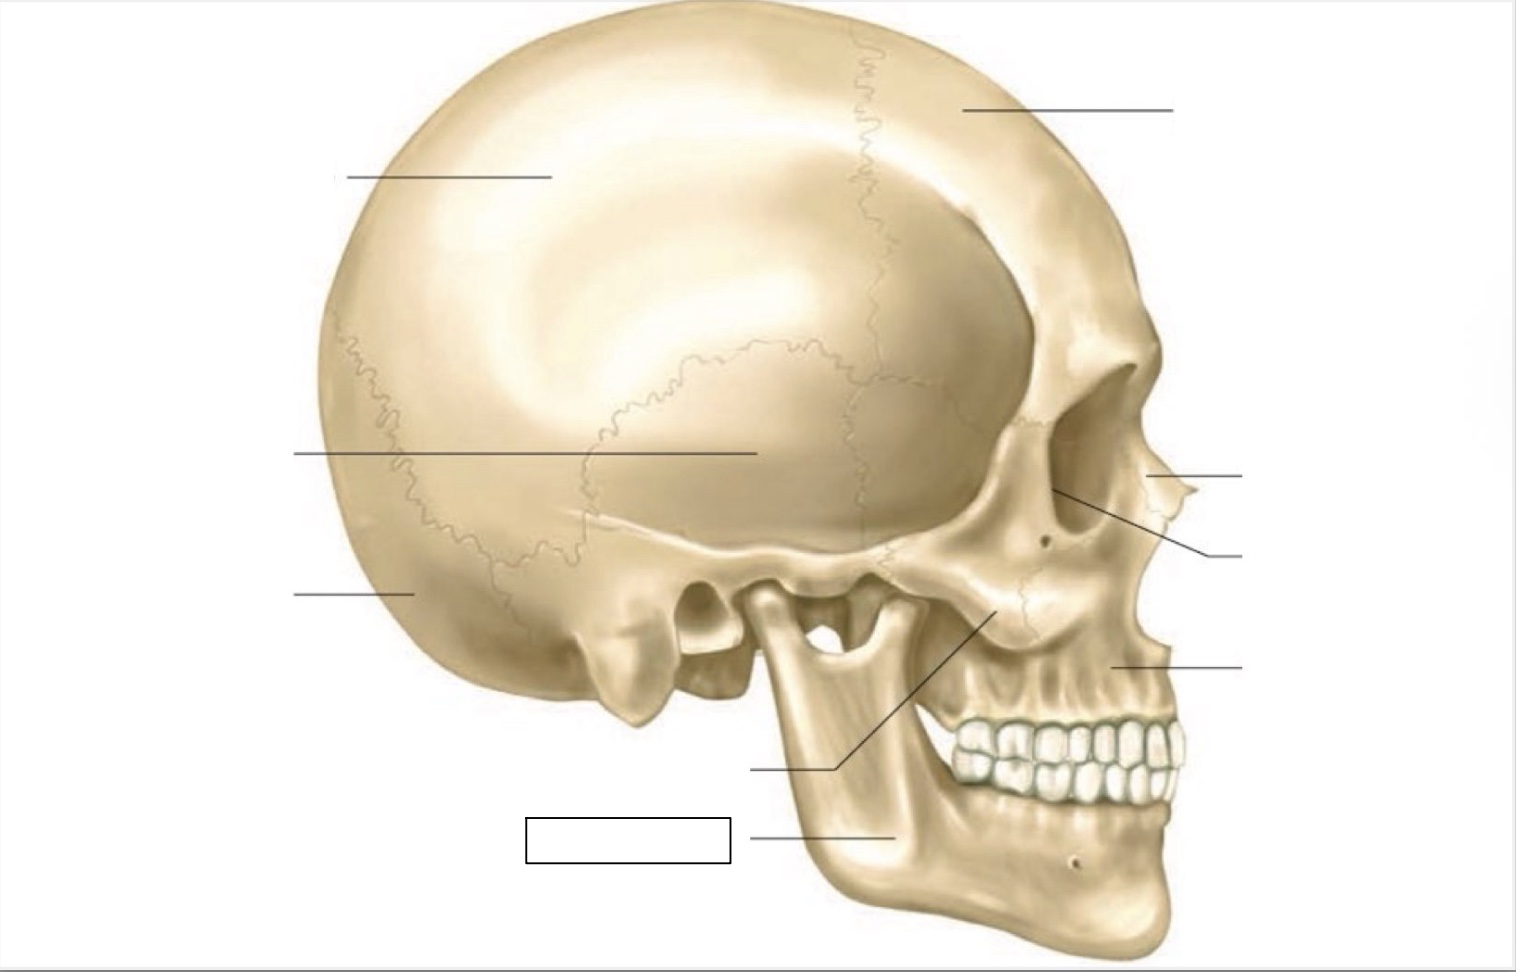

skull

frontal bone

nasal bone

orbit

maxilla

mandible

zygomatic bone

occipital bone

temporal bone

parietal bone